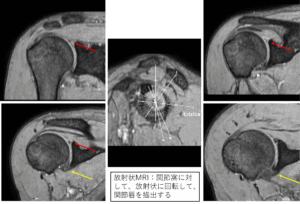

- MRI検査:肩関節唇損傷の状態を確認。他の疾患との鑑別が必要な場合に実施

赤矢印:上方関節唇損傷

赤矢印:上方から後方の関節唇損傷

黄矢印:前方の肥厚した関節唇